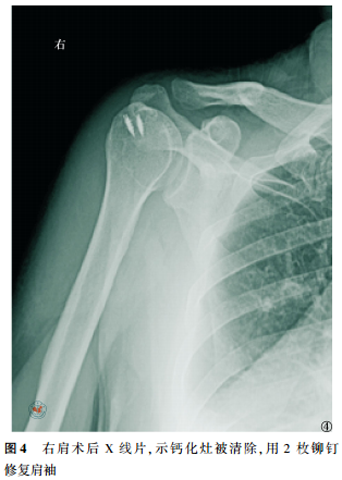

所有病例术后疼痛即刻消失,当晚夜眠良好。经过3~12个月的随访,UCLA评分由术前的(12.5±2.5)分提高至末次随访的(35.2±4.0)分,术前与末次随访比较,差异有统计学意义(t=5.317,P<0.05)。X线检查显示未见模糊的沉积病灶恢复清楚的边缘(图4);无1例发生肩关节僵硬、肩袖撕裂或新的钙化灶。

女性患者,49岁,因“右肩关节疼痛、活动受限5d”入院,查体见右肩关节局部压痛,以冈上肌处明显,右肩关节主动活动范围受限,被动活动范围基本正常,Neer撞击征(+),术前X线片示右肩峰下一巨大密度增高团块(图1),磁共振示右冈上肌腱内一信号增高团块(图2),诊断考虑“右肩关节钙化性肌腱炎”,行“右肩关节关节镜探查清理+冈上肌腱钙化灶清理+肩袖修补术”,术中清理右肩冈上肌腱内牙膏样的乳白色稠状物,即钙质沉积(图3),见肌腱裂口超过肩袖厚度的1/2,予2枚铆钉修补肩袖,术后复查右肩关节X片(图4)。术后患者疼痛程度明显减轻,随访9个月,UCLA评分由术前的11畅5分提高至33畅5分,且无出现术后并发症。